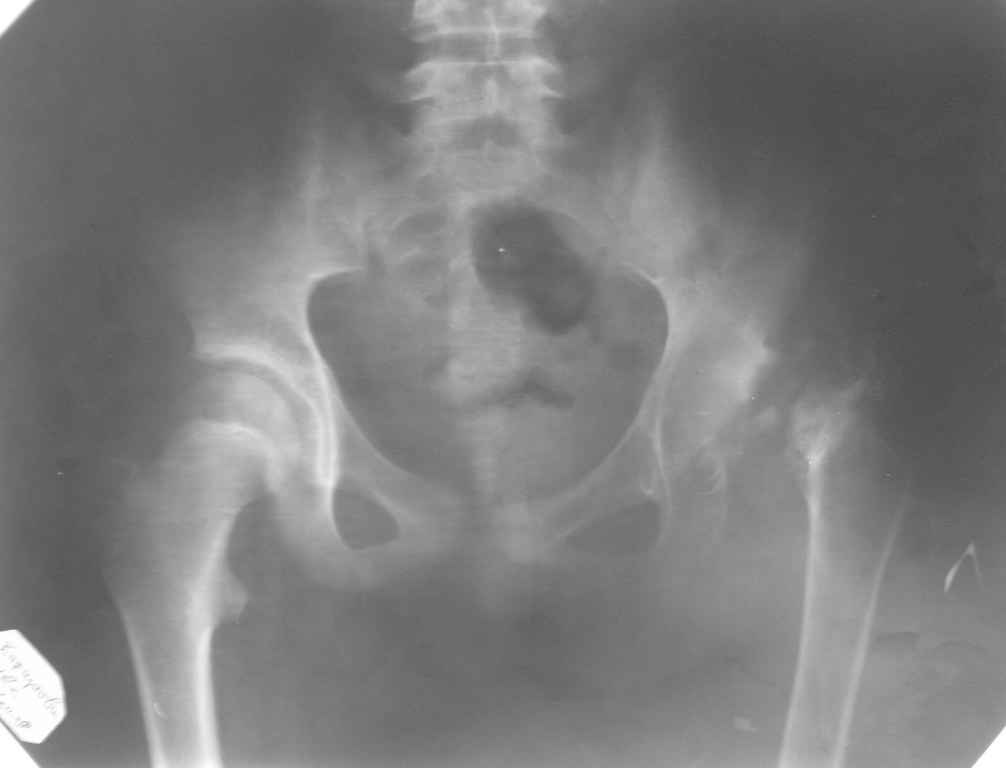

Re: ассептический некроз головки левой бедренной кости

Снимок во вложении по поводу АНГБ